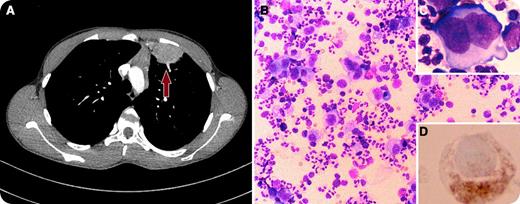

A 15-year-old young man presented to the emergency department with a 3-week history of sharp left-sided chest pain, shortness of breath on exertion, and a low-grade intermittent fever. Chest radiograph revealed increased density in the upper left lobe, thus he was treated with antibiotics for query pneumonia. Although his fever subsided, the patient continued to have chest pain, and subsequently developed night sweats and fatigue. Chest computed tomography revealed complex soft tissue, mostly located in his left lung, and minimally enlarged mediastinal lymph nodes (panel A). The differential diagnosis included sarcoma, congenital cyst, and lymphoma. The suspicious lung mass was resected for pathology. The cytospin results showed numerous large atypical cells in a background of neutrophils, eosinophils, lymphocytes, and histiocytes (panel B). The atypical cells often had abundant cytoplasm, and the nuclei often contained prominent nucleoli. Typical Reed-Sternberg cells are noted with a bi-lobed nucleus, giving the cell a typical “owl’s eyes” appearance (panel C). Cells showed CD30 positivity with immunohistochemistry stains (panel D).

A diagnosis of nodular sclerosis Hodgkin lymphoma stage IIB was made. The patient was started on adriamycin-bleomycin-vinblastine-dacarbazine combination chemotherapy, with favorable response. Primary pulmonary Hodgkin lymphoma is a very rare entity whose prognosis depends on its stage.